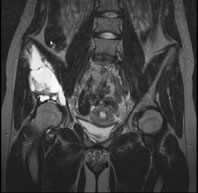

Die Röntgenuntersuchung von Becken/Hüfte zeigt eine septierte geographische Osteolyse in der Ala und im Korpus des Os Iliums rechts. Das Röntgenbild und die Aufnahmen der nachfolgenden MRI-Untersuchung sehen Sie hier:

T2 FS, coronar, 5 mm

Bild vergrössern